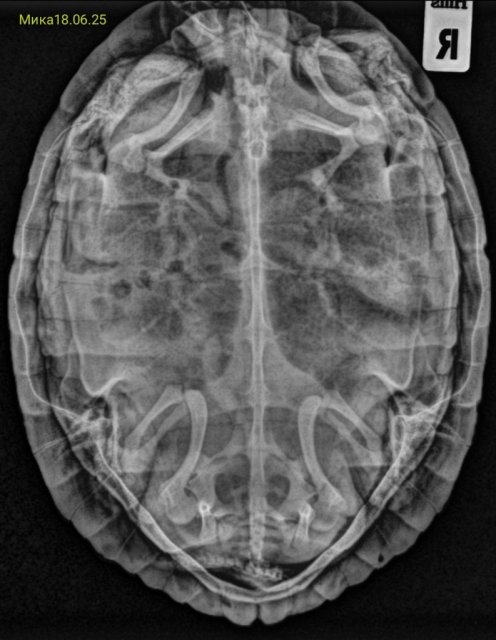

Собрала все её рентгены в кучу. Что можно сказать по последним двум, от 18 июня?

Screenshot_2025-06-23-20-49-43-211_com.vkontakte.android-edit.jpg

Screenshot_2025-06-23-20-44-46-266_com.miui.gallery-edit.jpg

Screenshot_2025-06-23-20-07-36-244_com.miui.gallery-edit.jpg

Screenshot_2025-06-23-20-06-00-118_com.android.chrome-edit.jpg